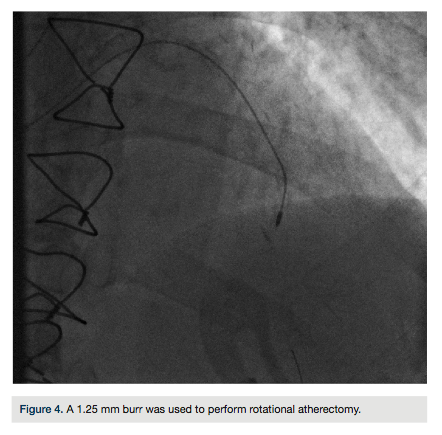

Given the angiographic findings, we elected to use a Rotablator (Boston Scientific) to facilitate stent delivery. A Runthrough wire (Terumo) was advanced and exchanged distally through an over-the-wire balloon for a Rota floppy wire (Boston Scientific). A 1.25 mm burr was used to perform rotational atherectomy (Figure 4). The wire was changed out to a